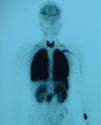

Caso 4Paciente de 11 años, trasplantada de hígado a los 7 meses de vida por atresia de vías biliares y en situación de cirrosis biliar por colangiopatía al momento de la consulta, que presenta episodios puntuales de cianosis central al correr y SaO2 basal del 93%. Al explorarla destacan acropaquias y cianosis labial. No presenta signos de dificultad respiratoria y la auscultación cardiorrespiratoria es normal. Ortodesoxia positiva. Hepatomegalia de 3cm. En la gasometría arterial (con FIO2 del 21%) se constata pH 7,46, PaCO2 de 27,5mmHg, PaO2 de 69mmHg, bicarbonato de 19,3mEq/l y exceso de bases de -3,2mEq/l. La espirometría forzada y la radiografía de tórax son normales pero en la ecocardiografía se aprecian 2 flujos sugestivos de fístulas, uno que desemboca en la aurícula derecha y el otro en la vena pulmonar izquierda. La gammagrafía pulmonar de perfusión muestra un cortocircuito de derecha a izquierda del 28% (fig. 3). En la angio-TC pulmonar se evidencia una fístula arteriovenosa periférica en el lóbulo inferior derecho. Tras el diagnóstico de SHP tipo 1 y 2, se realiza embolización de la fístula con coils, con mejoría parcial de la oxigenación, y posterior retrasplante hepático sin presentar complicaciones importantes tras su realización; se puede retirar a las 3 semanas el tratamiento con oxígeno.